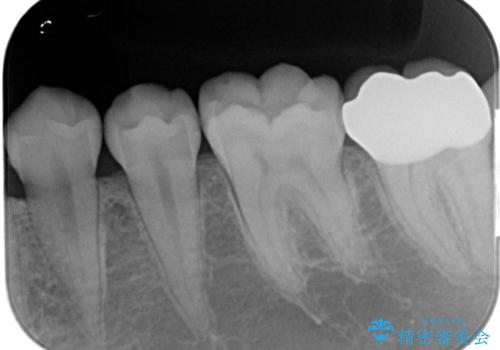

- 左下奥歯が痛いとの事で来院。

親知らずが炎症を起こしていたので抜歯をし、手前の歯は拡大鏡下で虫歯を取り除き、ジルコニアクラウンで治療をしました。

- ジルコニアクラウンスタンダード・仮歯 12.1万円 親知らず抜歯 保険適応費用は治療当時の料金となります